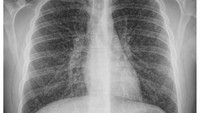

Foto X-ray remaja berusia 17 tahun di Kanada yang mengalami kondisi langka popcorn lung akibat kebiasaan menghisap vape. (Foto: Canadian Medical Association Journal)